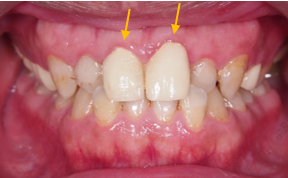

治療前 :前牙錯咬,上下排齒列不整,蛀洞大,左下缺牙空間大。

治療前:前牙臨時牙套顏色蠟黃,齒色不均。

牙齦覆蓋牙齒較多,笑齦。